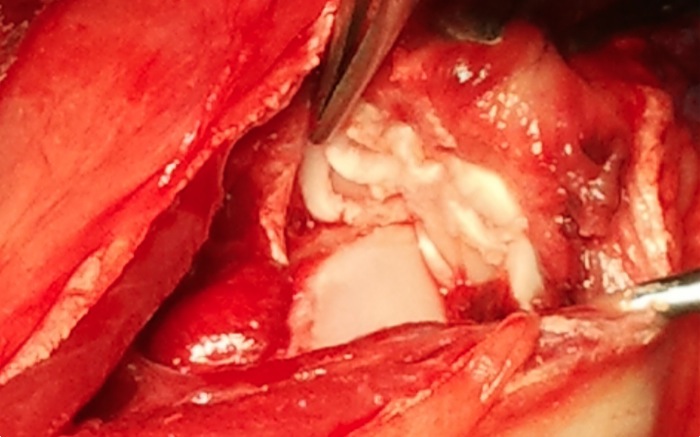

El abordaje articular se realiza desde la meseta tibial y en toda la amplitud de la cápsula. Explorarando los meniscos nos encontramos con una imagen de roturas múltiples de ambos, medial y lateral. La reparación o menisquectomía parcial no son posibles.

A pesar de las tensiones soportadas el LCC no está roto completamente. Se decide ante la importante lesión su retirada completa desde su origen a inserción en la meseta.